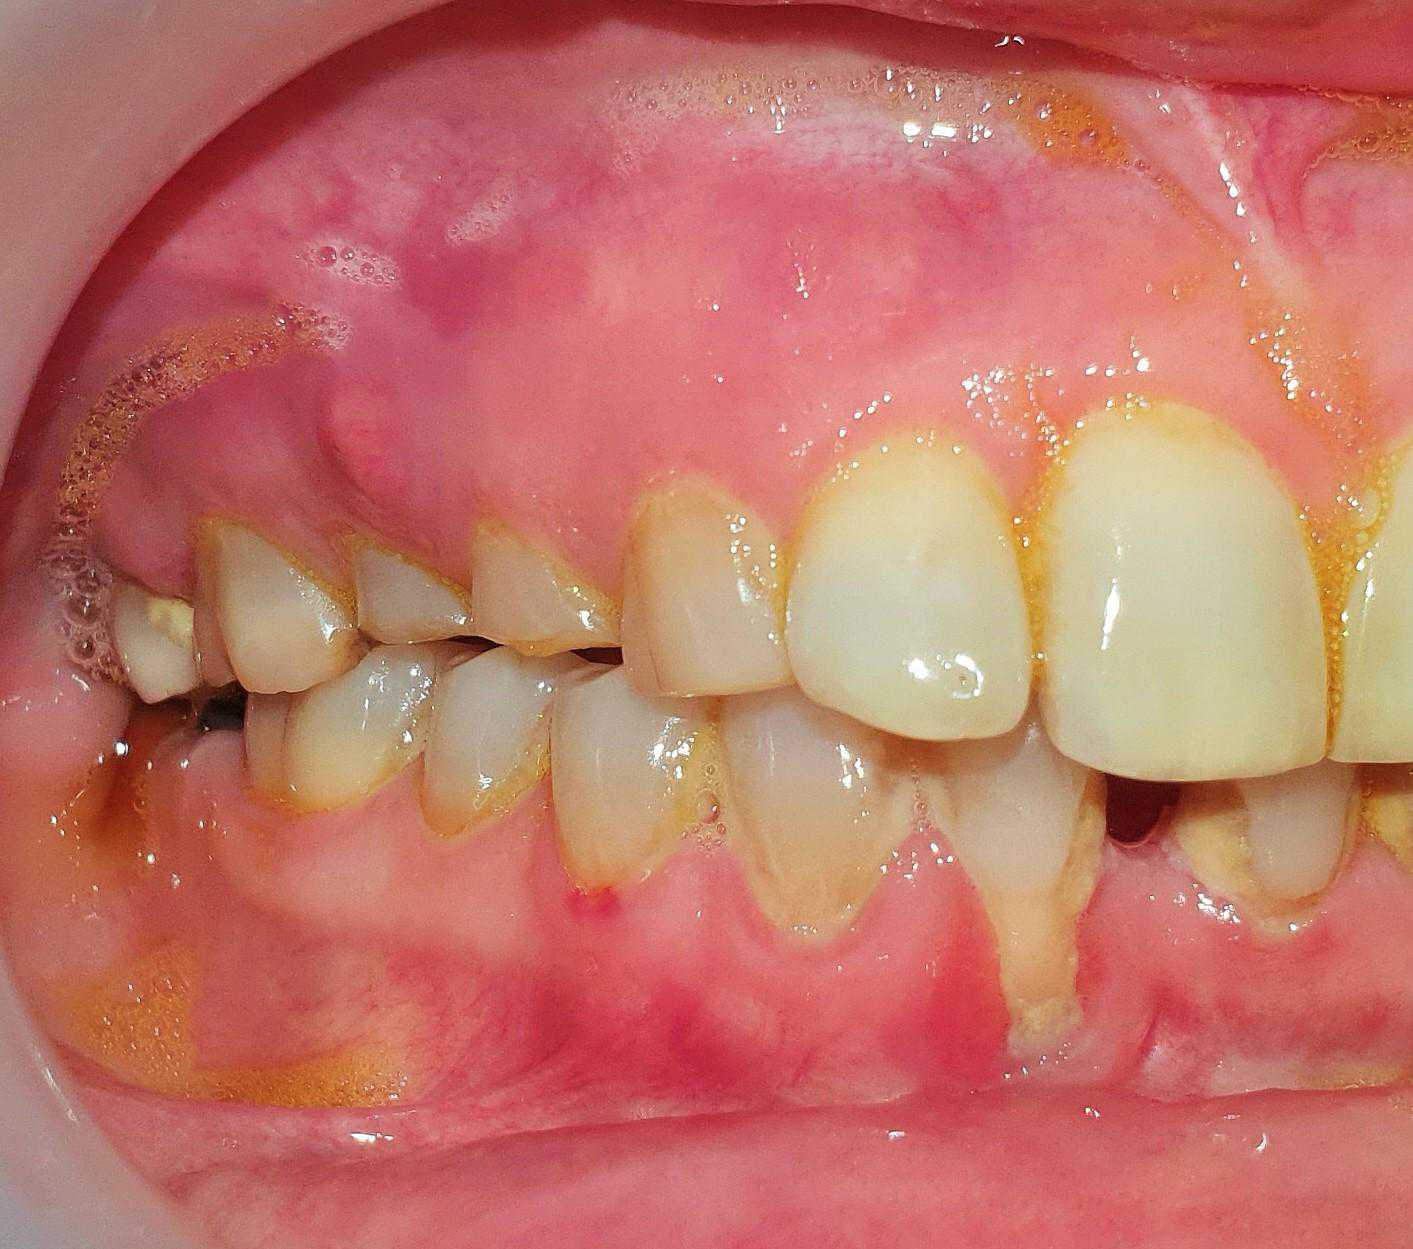

This is a case of Ameloblastic Fibro-Odontoma with a long term follow up.

https://demo.discussdentistry.com/forums/topic/should-surgery-be-done-at-13-years-of-age/#post-24451 <![CDATA[Should surgery be done at 13 years of age ?]]> https://demo.discussdentistry.com/forums/topic/should-surgery-be-done-at-13-years-of-age/#post-24451 Wed, 27 Oct 2021 08:03:10 +0000 site_admin Male patient . Age 13 years. No relevant medical history